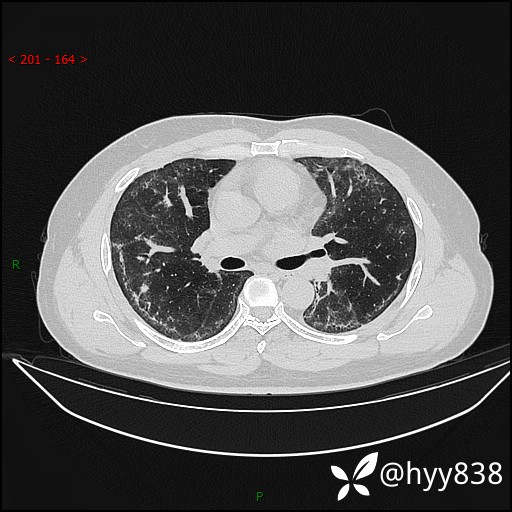

辅助检查:CT

临床诊断:间质性肺炎

第一次胸部CT